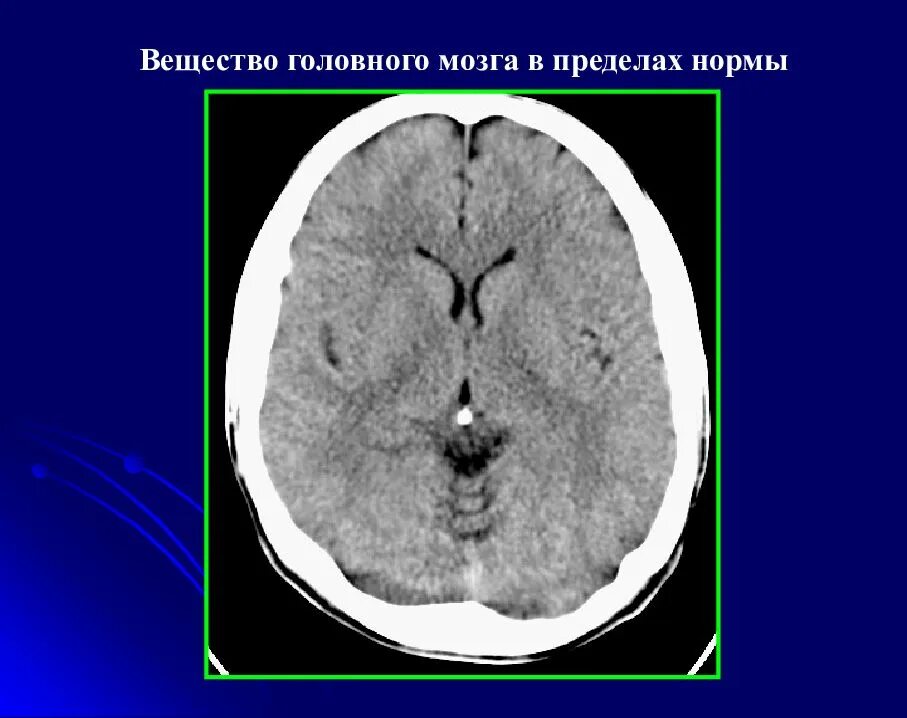

Норма кт